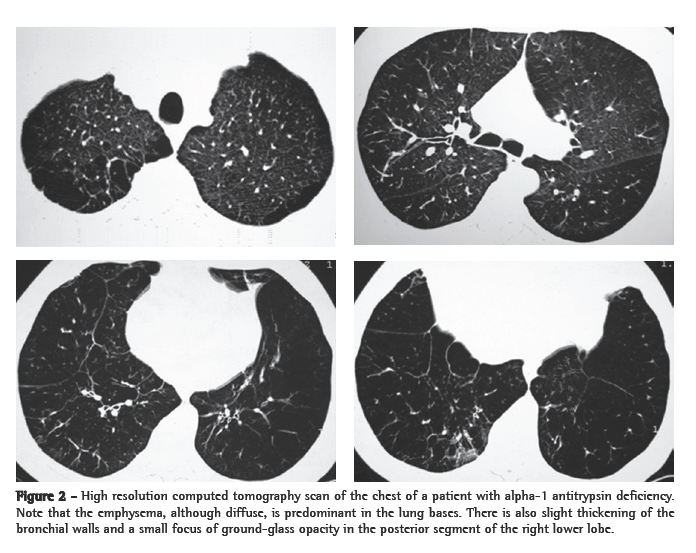

High-resolution computed tomography (HRCT) of the chest (Figure 2) is a method that is more sensitive for the detection of pulmonary disease than are routine X-rays, pulmonary function tests, or clinical profiles.(28) The characteristic pattern is panlobular emphysema, which represents a simplification of the lung architecture, with decreased attenuation of the lung parenchyma on X-rays and decreased blood vessel number and diameter. Tomographic alterations are also classically described as being predominant in the lung bases, although it is important to emphasize that, in up to 36% of the cases, they can extend to the lung apices and can occasionally present apical predominance. Bullae are less common than in smoking-related emphysema. Bronchiectasis can also be present.(3,28)

The degree of impairment observed on chest HRCT scans presents a favorable correlation with anatomopathological and pulmonary function findings, and, therefore, HRCT has been proposed as a method for the follow-up evaluation of the progression of emphysema. However, this application is limited by difficulties in the reproducibility of sequential tests, particularly those related to the intensity of inspiration, which directly influences the radiological density of the parenchyma.(28) At the moment, there is no formal recommendation regarding the need for tomographic follow-up evaluation of the disease, and the question of whether or not tomography is inedicated should be addressed on a case-by-case basis.(3)